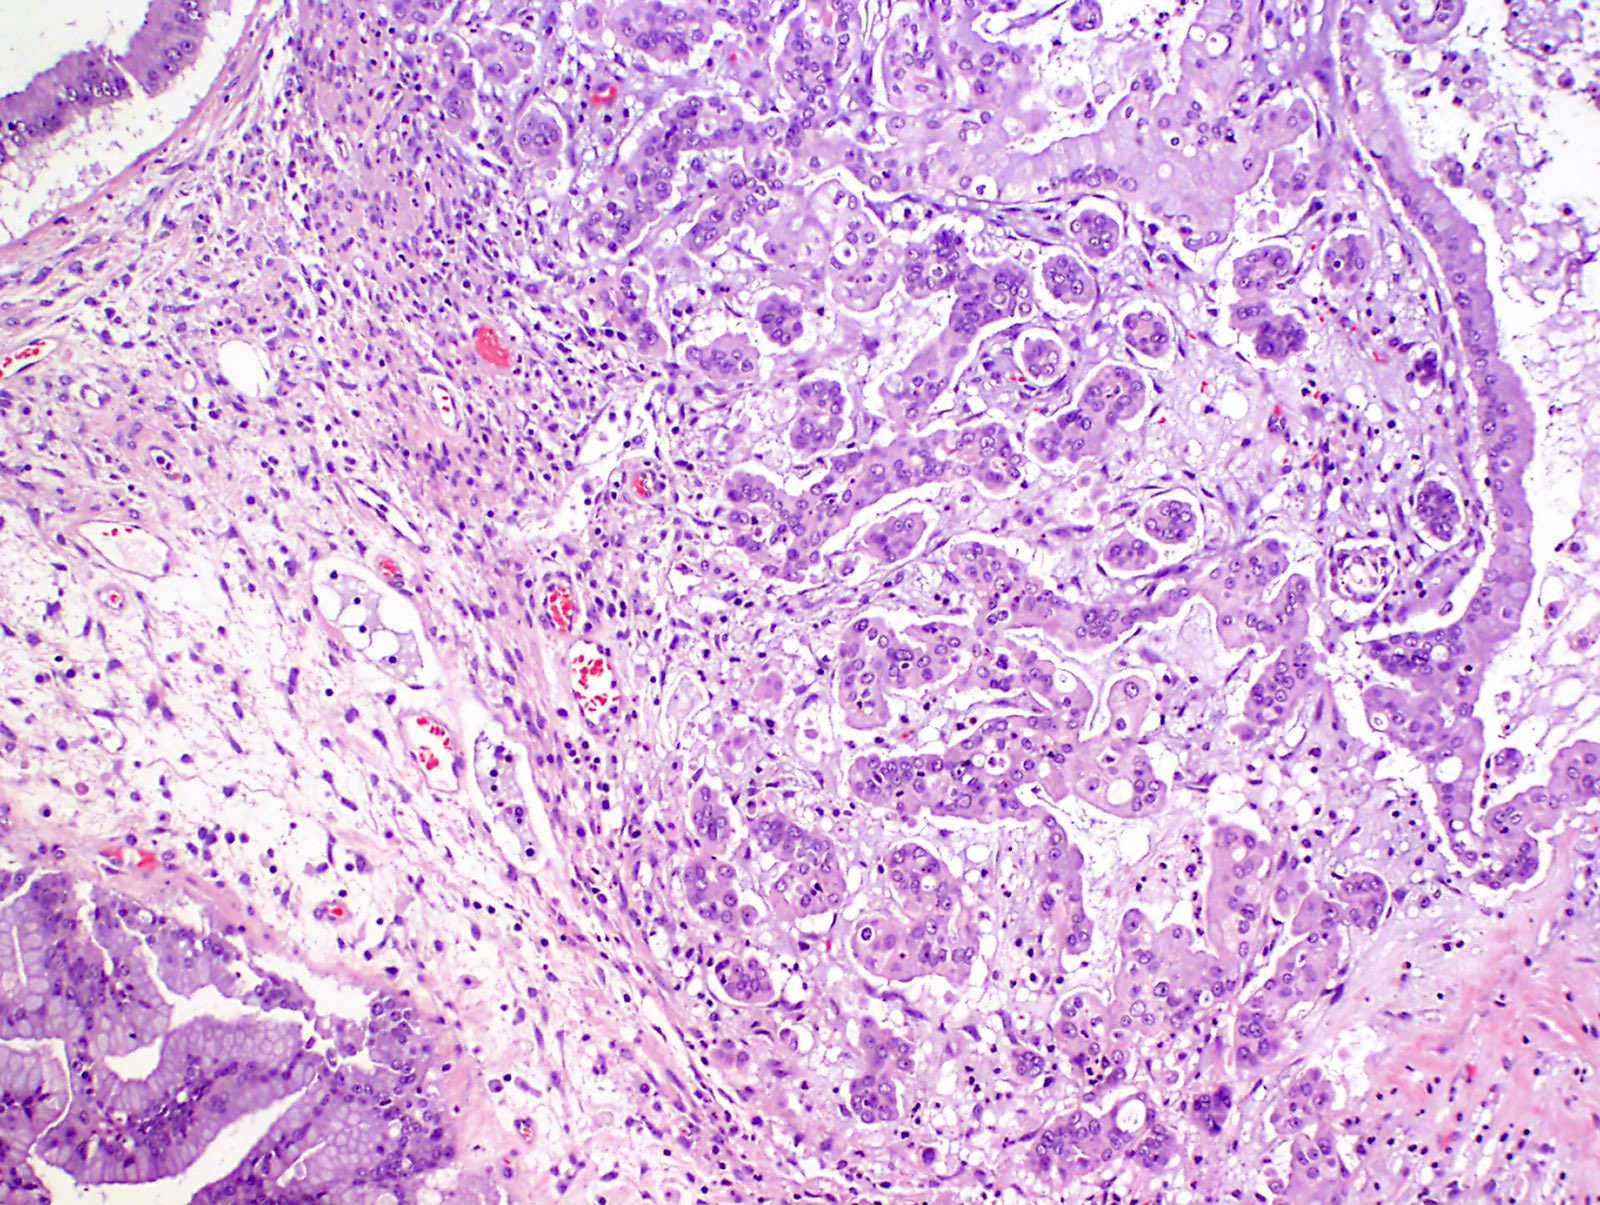

Histological findings of the endometrioid borderline ovarian tumor